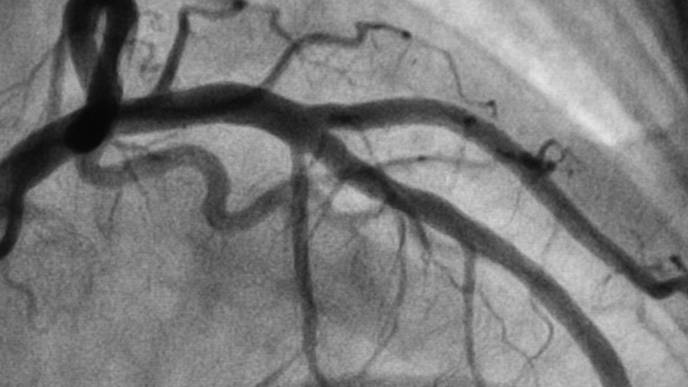

The trial focused on patients with angina, or chest pain due to plaque buildup in the coronary arteries, that is not adequately controlled with available treatments. The CSR is an hourglass-shaped stent designed to narrow the vein that collects blood from the heart muscle (the coronary sinus) and drive oxygen-rich blood back into areas of the heart muscle that may not be receiving enough blood.

All participants had symptomatic angina, ischemia and coronary artery disease with no further medical or interventional options at the start of the study. Participants underwent a cardiac MRI and treadmill exercise test before their procedure and at the end of a blinded six-month follow-up period. Patients also recorded their angina symptoms daily with a smartphone application.

The trial had two primary endpoints: angina symptoms as assessed with the smartphone application and blood flow to the heart assessed with a cardiac MRI. At six months, participants who received the CSR implant were 40% more likely to report a reduction in the number of daily angina episodes than those who received the placebo procedure; however, they showed no difference in terms of overall blood flow to the heart.